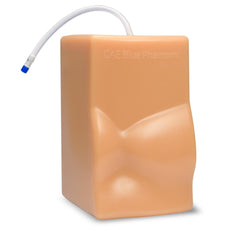

Gain proficiency in performing transvaginal ultrasound exams with our CAE Blue Phantom female pelvis models. The patented Simulex internal tissue allows learners to develop, practice and verify ultrasound imaging skills, including using ultrasound system controls, positioning and moving the transducer, recognizing internal pelvic anatomy and pathology and using gynecological ultrasound calculation packages to measure cysts, masses, and other structures. These models are excellent for 2D, 3D, and 4D ultrasonography imaging techniques. Choose from three options: General Pathology, Intrauterine & Ectopic Pregnancy, or Sonohysterographay & Sonosalpingography.

Sonohysterography & Sonosalpingography ANATOMY:

- Endovaginal canal

- Cervix

- Cervical canal

- Uterus

- Endometrial canal

- Fibroids

- Bladder

- Patent fallopian tubes

- Bowel